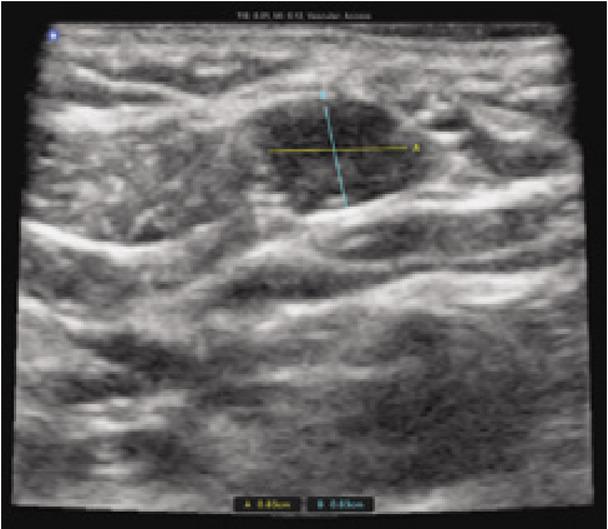

Fig. 2

Short-axis view of a second branchial cleft cyst

A 31-year-old female with no past medical history presented to the emergency department with the chief complaint of a “hole” in her neck that had been present since childhood, with no previous workup or diagnosis. The patient described intermittent, clear fluid of varying consistency draining from the site. She denied any recent illness, fever, pain, swelling, numbness, dysphagia, and dysphonia. Her speech was clear without hoarseness. On examination, a small, approximately 2 mm defect in the skin of the right lower neck, located just anterior to the SCM, was present. The skin around the area was normal in color, without erythema or purulent drainage, and was smooth to light palpation, with no mass appreciated on deep palpation (Fig. 1). No cervical lymphadenopathy was present. Cranial nerve examination was within normal limits. A handheld ultrasound system was used to evaluate the area of interest with a single, multi-frequency, capacitive micro-machined ultrasonic transducer (manufacturer: Butterfly IQ). A vascular access setting, roughly equivalent to a high-frequency linear piezoelectric transducer, was used to identify a well-defined, hypoechoic, heterogeneous, cyst-like structure with a thin, enhancing rim and moderate posterior acoustic enhancement that had a short axis length greater than 0.83 cm × 0.63 cm, and was approximately 0.4 cm deep to the skin at the most superficial aspect (Fig. 2 and Fig. 3). Color flow Doppler did not demonstrate any blood flow within the structure. After thorough ultrasound evaluation, a fistula tract was unable to be visualized; however, given the history of secretions and the presence of an obvious skin defect overlying the structure, a fistula tract to the underlying structure was felt to be likely present. Given the history, physical examination findings, and point-of-care ultrasound imaging, the diagnosis of a second branchial cleft sinus was made. The patient provided written consent for images and publication of this case.